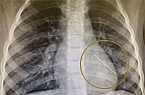

Ayala, a 3.5-year-old girl, was playing at home with her 5-year-old sister when, during the game, she inserted a small button battery into her nose. Only hours later, after Ayala's father blew her nose and observed a dark, suspicious discharge, did the parents realize the severity of the situation and rushed to the Emergency Medicine Department at Schneider Children'sRead more...